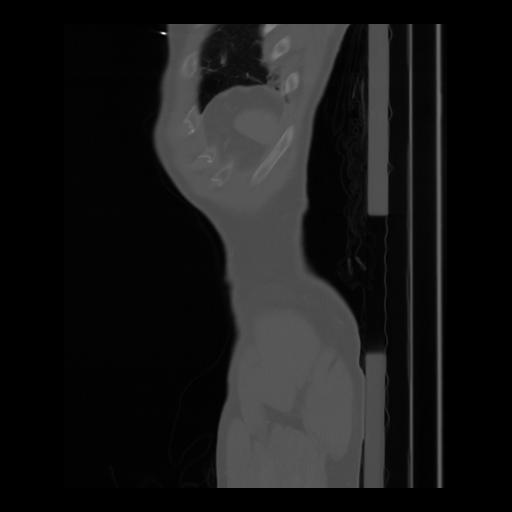

36 CUERPO,CE,Sagittal,3.000,CUERPO,Sagittal,